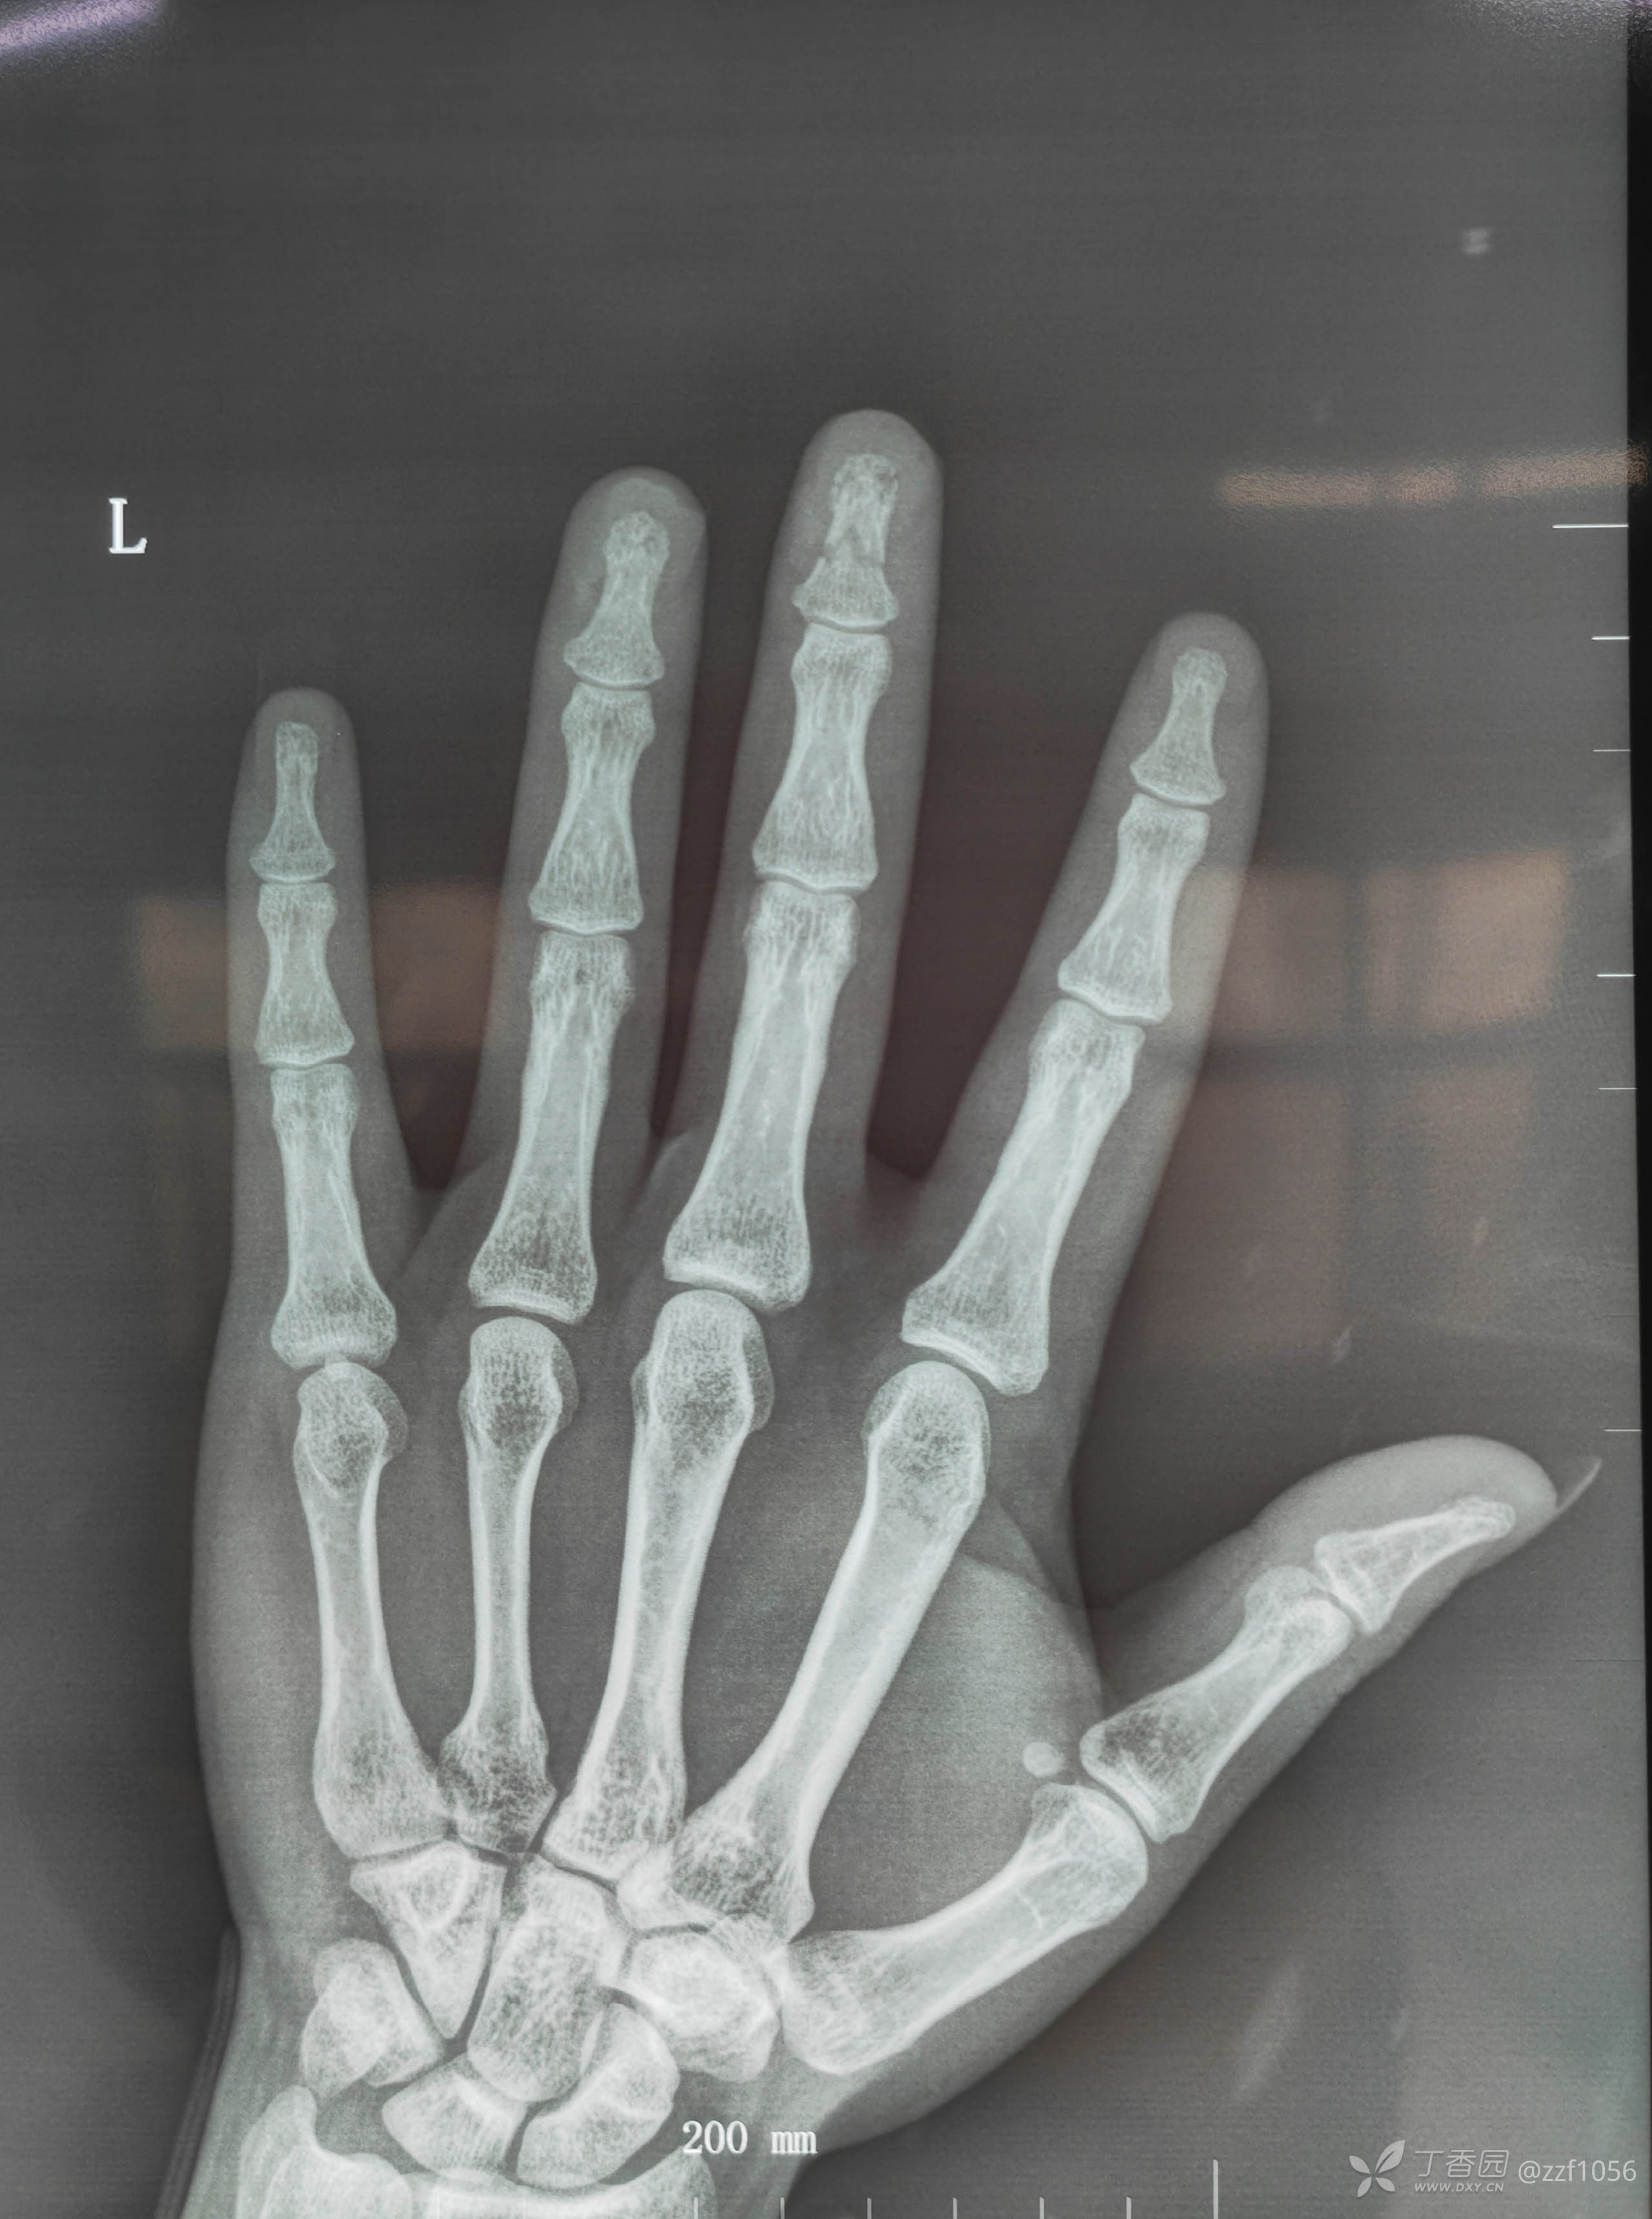

指骨骨折小细节,指甲需要回植吗?

武医生 等 3 位达人已点赞齐某某,男,29岁,夹伤,急诊手术

背侧成角折端嵌插千万不要以为直接就可整复,经验告诉我们闭复肯定会失败

指骨骨折临床多见,不算复杂,但是小病例也不简单,做好也需要小技巧,分享给手外初学者的兄弟。